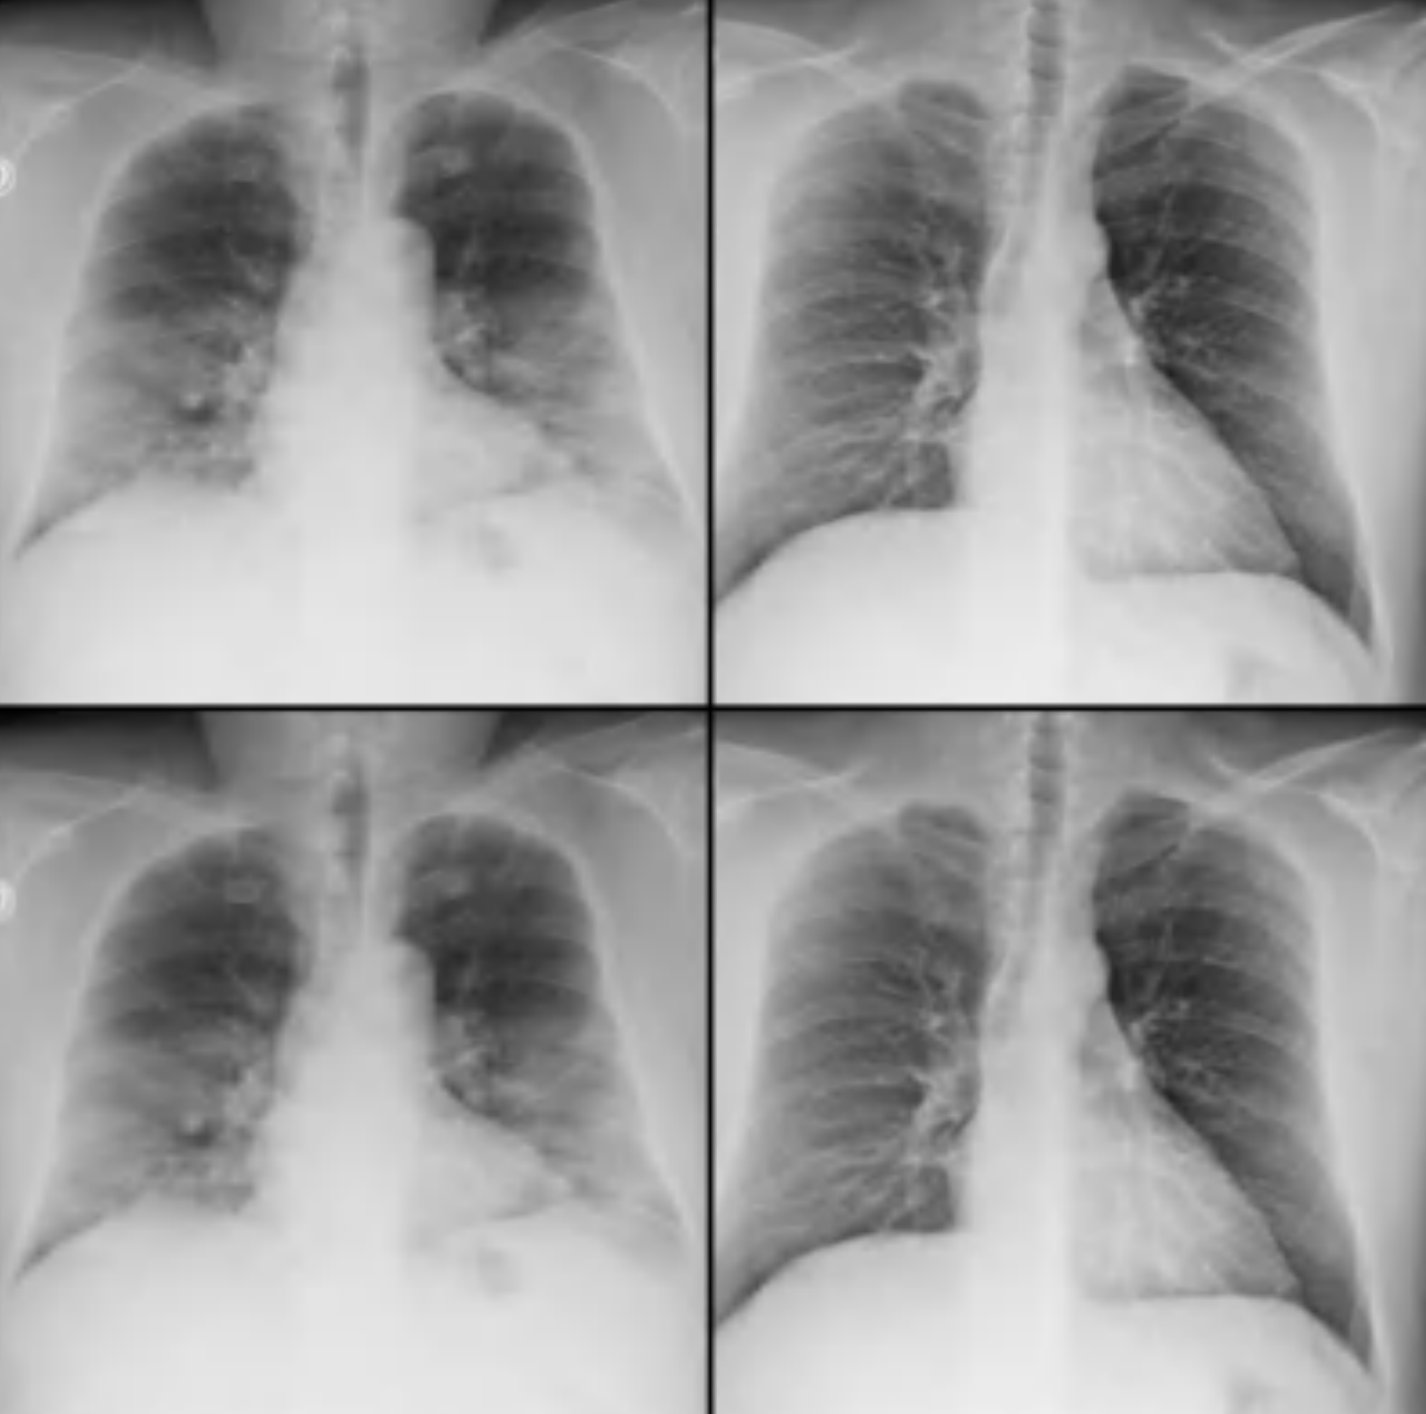

Deep Learning for Medical Imaging

2020

A uni-project implementing deep learning for COVID-19 detection from chest X-rays at the height of the pandemic.